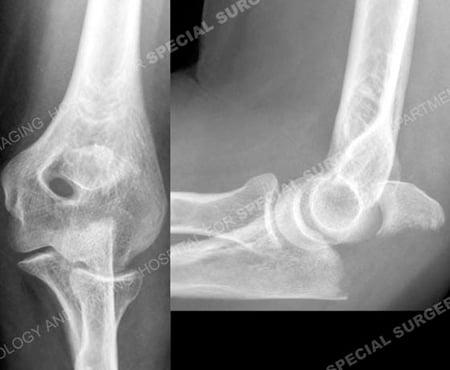

Anteroposterior and lateral radiographs revealing an ulna olecranon fracture.